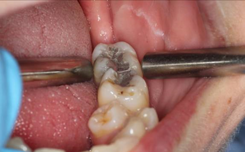

Measurement of furcation involvement

Damage from periodontitis can lead to furcation involvement of multi-rooted teeth. This can be measured using a furcation probe (see figure: Nabers furcation probe) and graded depending on the severity of the furcation involvement28 (see table: Grading of furcation involvement).